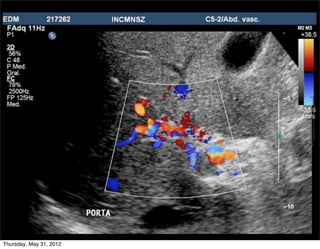

Porta normal

LAMINAR: petal y ligeramente ondulante

• Flujo normal (petal)

• Hacia el transductor (rojo)

(excepto rama posterior der –

azul -)

• Variante: flujo helicoidal

Porta común